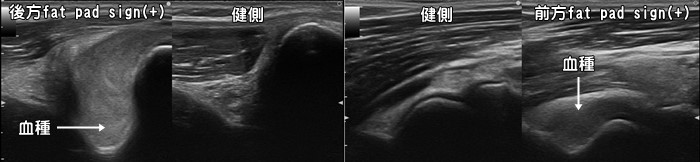

肘関節捻挫・打撲・Fat pad sign

転倒して手をついたり、肘関節を直接強打するなど比較的強い力が加わると関節内に血が溜まります。肘関節は関節包と呼ばれる袋に包まれていてそこに血腫が貯留します。エコーではFat pad sign(ファットパッドサイン)と呼ばれます。Fat pad signが確認された場合、小児では上腕骨顆上骨折、大人では橈骨頭・頚部骨折を強く疑います。レントゲンでは写らない骨折(occult fracture)もあるため非常に重要なサインです。血腫の量が多い場合は針で穿刺・吸引します。